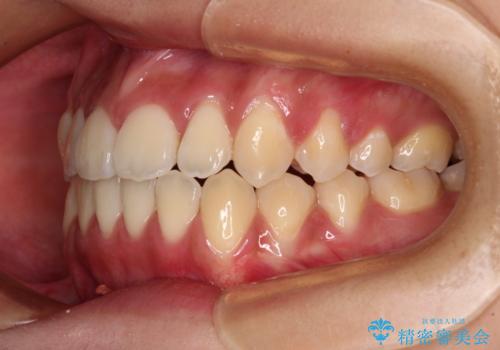

受け口と開咬を急速拡大装置とワイヤー装置で改善

- 前歯の開咬と、受け口による咬み合わせの悪さを気にして来院された患者様です。

上顎歯列が狭窄していたため、急速拡大装置により上顎骨を側方に拡大し、その後ワイヤー装置にて矯正治療を行うこととしました。